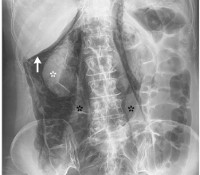

Прободение толстого кишечника диагностируется проктологом на основании жалоб, данных физикального осмотра, инструментальных и лабораторных исследований. Постановка диагноза «перфорация толстой кишки», как правило, не вызывает затруднений. Симптомы острой абдоминальной катастрофы дополняются данными рентгенологических исследований, свидетельствующих о наличии свободного газа в брюшной полости. На обзорных рентгенограммах, выполненных в положении стоя, газ обычно хорошо просматривается под диафрагмой. При невозможности выполнить рентгенографию в положении стоя пациента с подозрением на перфорацию толстой кишки укладывают на бок и оставляют на несколько минут, чтобы газ успел переместиться и лучше просматривался на снимках.

При перфорации толстой кишки, возникшей вследствие кишечной непроходимости, на снимках могут обнаруживаться чаши Клойбера (затемнения в виде перевернутых чаш с горизонтальным уровнем жидкости под раздутыми газом участками кишечника). В сомнительных случаях осуществляют перитонеальный лаваж с последующим исследованием жидкости на содержание крови, кишечного содержимого, бактерий и лейкоцитов. Лабораторные анализы в первые часы после перфорации толстой кишки обычно малоинформативны. Отмечается лейкоцитоз со сдвигом влево. При развитии перитонита выявляются электролитные расстройства. При нарушении функций печени и развитии острой почечной недостаточности обнаруживаются соответствующие изменения со стороны крови и мочи.